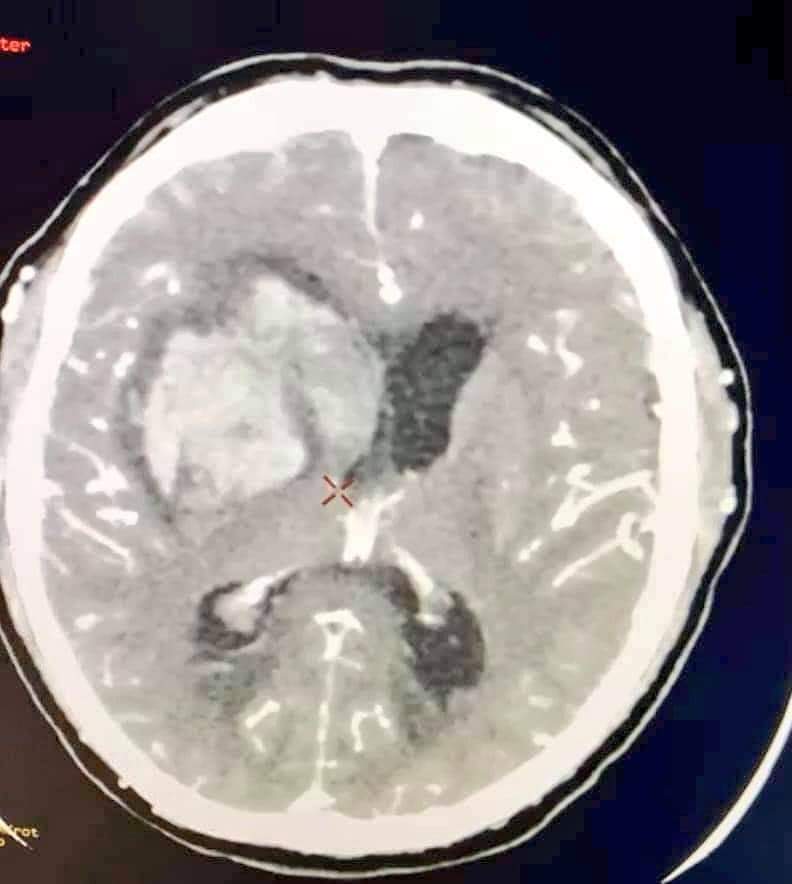

Tras su atención por el grupo de especialistas que se encuentran en primera línea de atención COVID, entre los que se incluyen neurocirujanos, se solicitaron estudios de tomografía, donde se encontró una hemorragia en los núcleos de la base del cerebro ocasionando hidrocefalia al obstruir las cavidades profundas del cerebro.

Lo anterior, ameritó someter al paciente a un procedimiento de urgencia, mediante una cirugía de mínima invasión para drenar la sangre acumulada y limitar daños graves.

“La hemorragia estaba ocasionando presión a su cerebro, comprometiendo el funcionamiento de este, con posibles secuelas a largo plazo o inclusive la muerte de no haber sido tratada oportunamente”, detalló el director normativo de Salud, Ramiro López Elizalde, quien como especialista estuvo pendiente de la evolución del paciente hasta que salió del hospital.

El procedimiento quirúrgico consistió en retirar el hematoma o masa de sangre producto de la hemorragia a través de un orificio en el cráneo del tamaño de una moneda, con la guía de un ultrasonido en tiempo real, para extraer cuidadosamente los restos de sangre y evitar tocar estructuras importantes del cerebro.